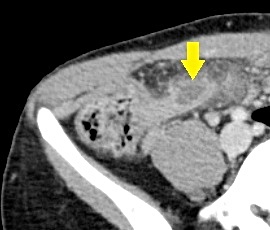

急性腹症のため救急受診。精査の結果、急性虫垂炎および限局性腹膜炎と診断。緊急手術(腹腔鏡下虫垂切除術)を施行した。病理結果は急性虫垂炎であった。

CT画像